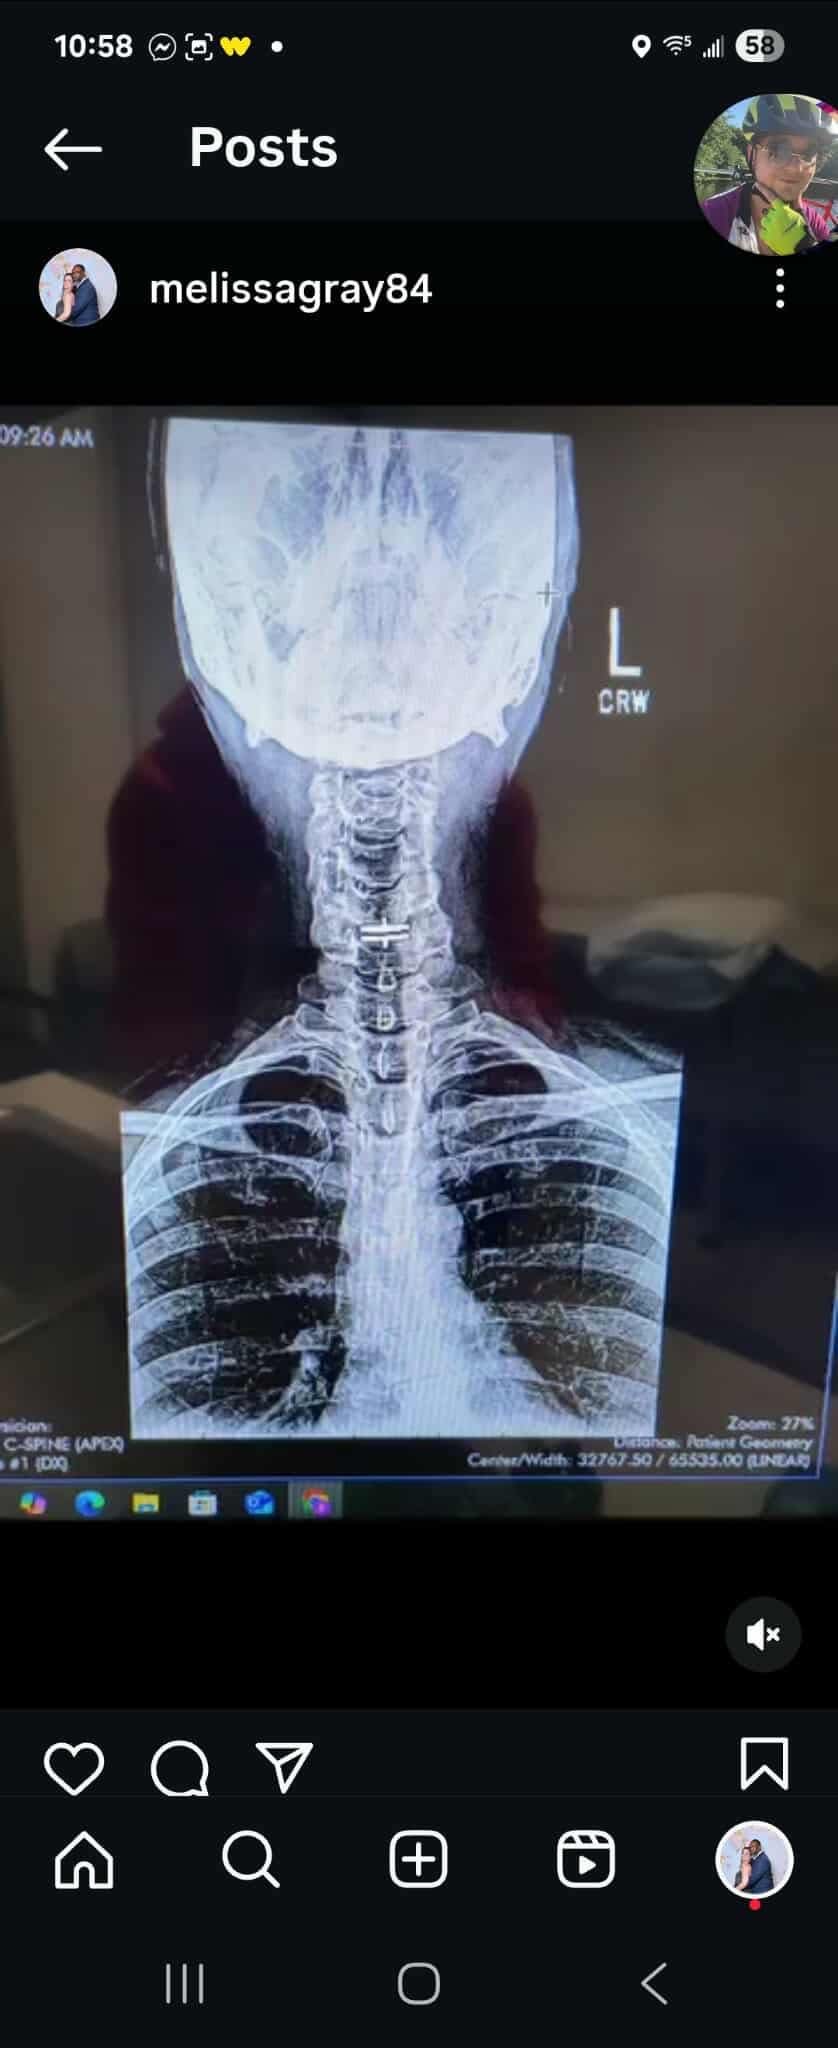

Hi I'm raising money for my friend and former coworker Melissa Brown, a hard worker, talented human being, and loving mother who has been going through a lot this last year. From neck surgery (cervical anterior arthroplasty total disc single level) to diagnoses such as P.O.T.S., E.D.S., M.C.A.S., sleep apnea, hernia, P.C.O.S. and more, there are countless medical bills from appointments, tests, hospitalizations, and medications. The cherry on top? Her health has recently declined to the point she can no longer work unless it's from home.